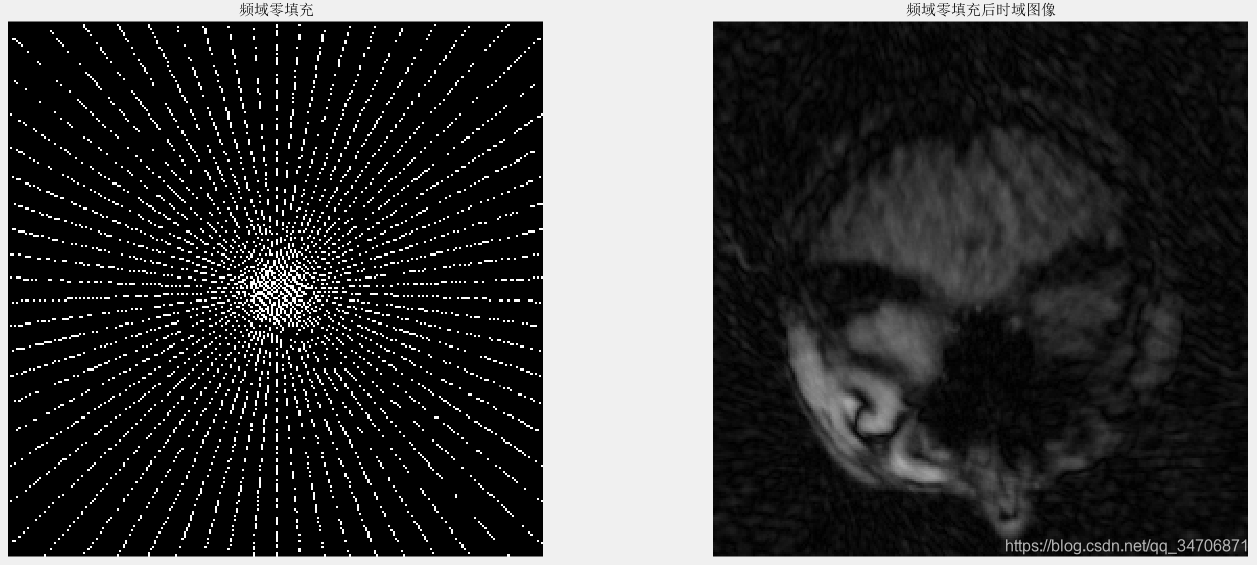

我们主要关注的是第三个方法,欠采样——>再重建。由欠采样图像去重建一幅全采样图像(真实图像),显然是一个NP难的问题(很多全采样图像能对应同一幅欠采样图像)。由于欠采样违反了奈奎斯特采样定理,直接进行频域零填充的时域图像上会发生混叠伪影,如图1、2、3所示。